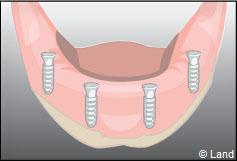

Exemple d’une réhabilitation complète implantaire

Deux techniques sont possibles. Elles font appel à la barre de rétention ou aux boutons-pressions.